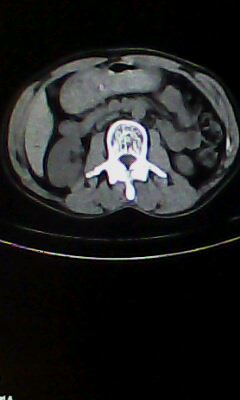

胰尾部占位?

未见明显异常。“胰尾占位”为肠管

口服造影剂是必须的